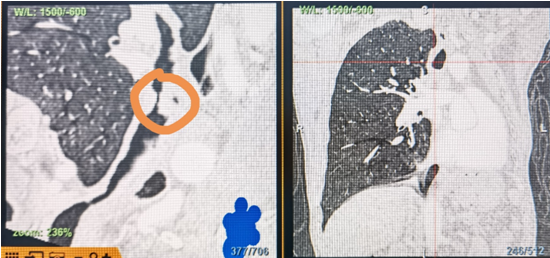

時(shí)間就是生命!了解患者病情后,歐陽海峰立刻啟動氣道梗阻緊急救治通道,協(xié)調(diào)院前轉(zhuǎn)運(yùn),急診快速入院流程。凌晨患者入院胸部CT顯示,現(xiàn)存唯一的呼吸通道在右主支氣管處,狹窄處僅約3毫米,患者命懸一線!

運(yùn)用呼吸介入技術(shù),軟硬鏡結(jié)合快速開通氣道,是患者目前唯一可行的治療方案,手術(shù)刻不容緩!但存在麻醉后氣道完全塌陷閉合、大出血、窒息等巨大風(fēng)險(xiǎn)。患者此前接連轉(zhuǎn)診3家醫(yī)院,均建議保守支持治療或轉(zhuǎn)院。歐陽海峰詳細(xì)了解患者病史,全面評估影像檢查結(jié)果后,決定盡快進(jìn)行手術(shù),組織醫(yī)護(hù)團(tuán)隊(duì)對患者進(jìn)行持續(xù)密切監(jiān)測,充分保障其術(shù)前安全。